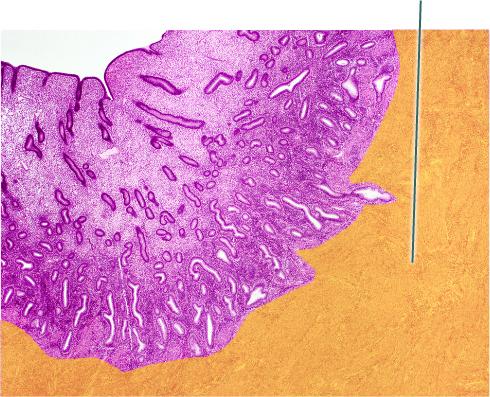

Identify the highlighted tissue in the vaginal wall.

Stratified Squamous Epithelium

Identify the highlighted structure.

Mature Tertiary Follicle

The highlighted structure is derived from which membrane?

Peritoneum